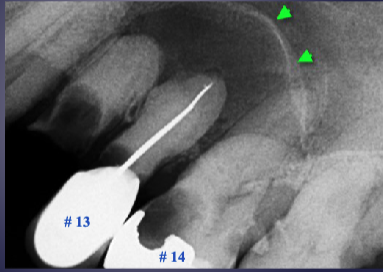

what’s the pathology of #7

apical rarefying osteitis

what’s the arrow pointing to

periosteal new bone formation

what are the arrows pointing to

“Halo sign”: elevation/displacement of max sinus floor